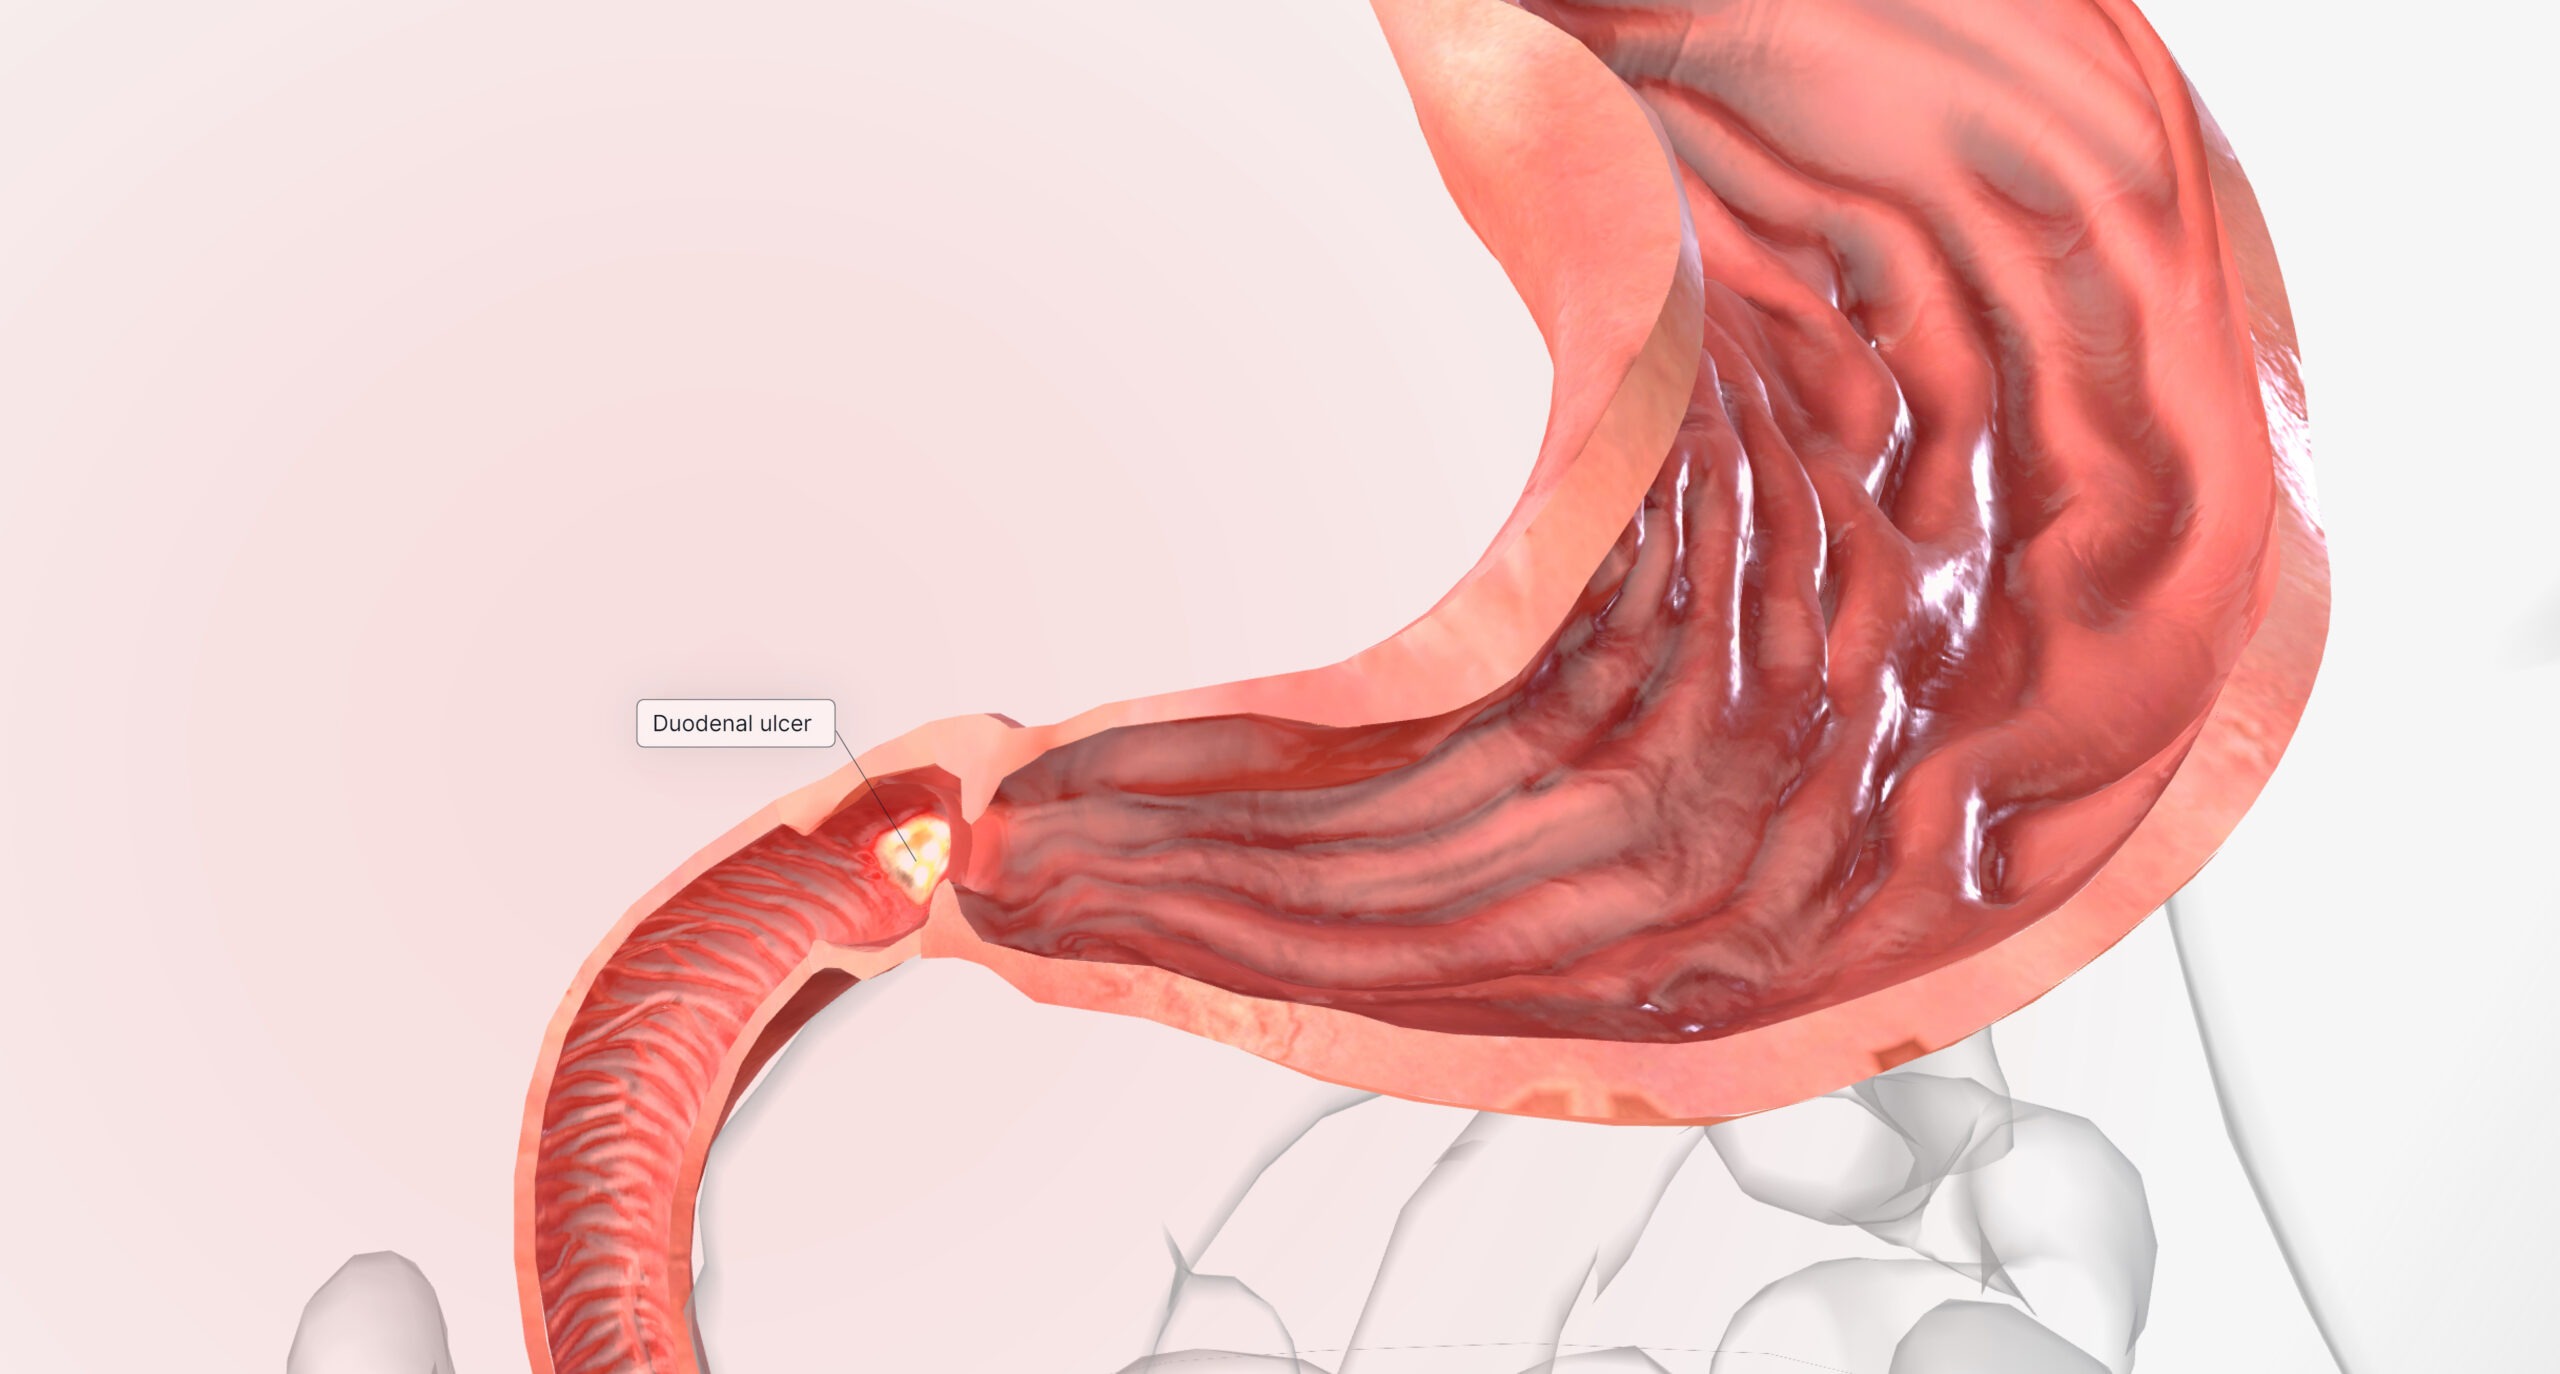

胃溃疡是指胃或十二指肠内壁的一种病理性损伤,形成溃疡。这些溃疡可以导致疼痛、消化不良、甚至出血。

胃溃疡的常见原因包括长期使用非甾体抗炎药(NSAIDs)、幽门螺杆菌感染、过度饮酒、吸烟以及过度压力。症状可能包括上腹部疼痛、饱胀感、反酸、恶心和体重减轻。治疗方案通常包括药物治疗来减少胃酸产生、消除幽门螺杆菌感染,以及改变生活方式。然而,在某些情况下,如药物治疗无效、出现并发症(如出血、穿孔或梗阻)时,可能需要进行手术治疗。

手术治疗胃溃疡主要针对那些对药物治疗反应不佳或出现严重并发症的患者。手术可以有效移除溃疡,阻止出血,修复穿孔,并在必要时去除阻塞的部分,以恢复正常的胃肠功能。